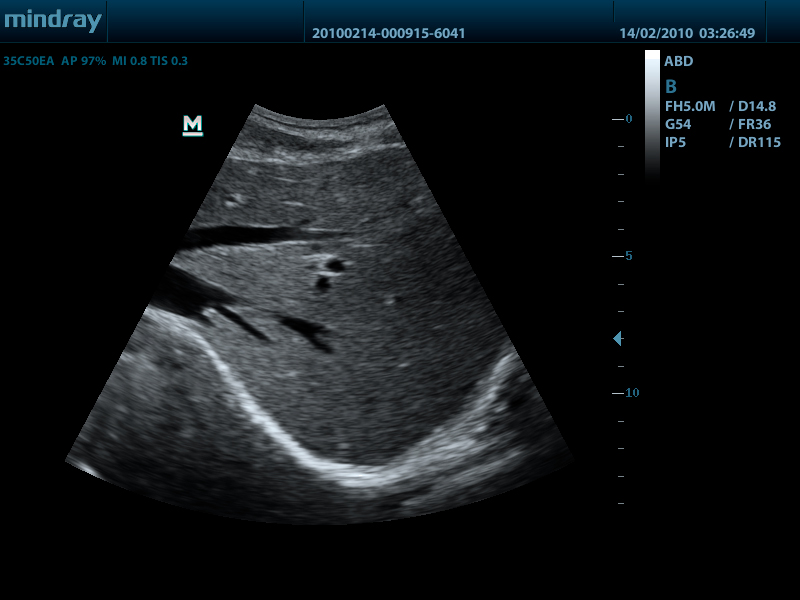

- Конвексный датчик 35C50EA, 1.7 - 6.0 МГц, радиус кривизны 50 мм